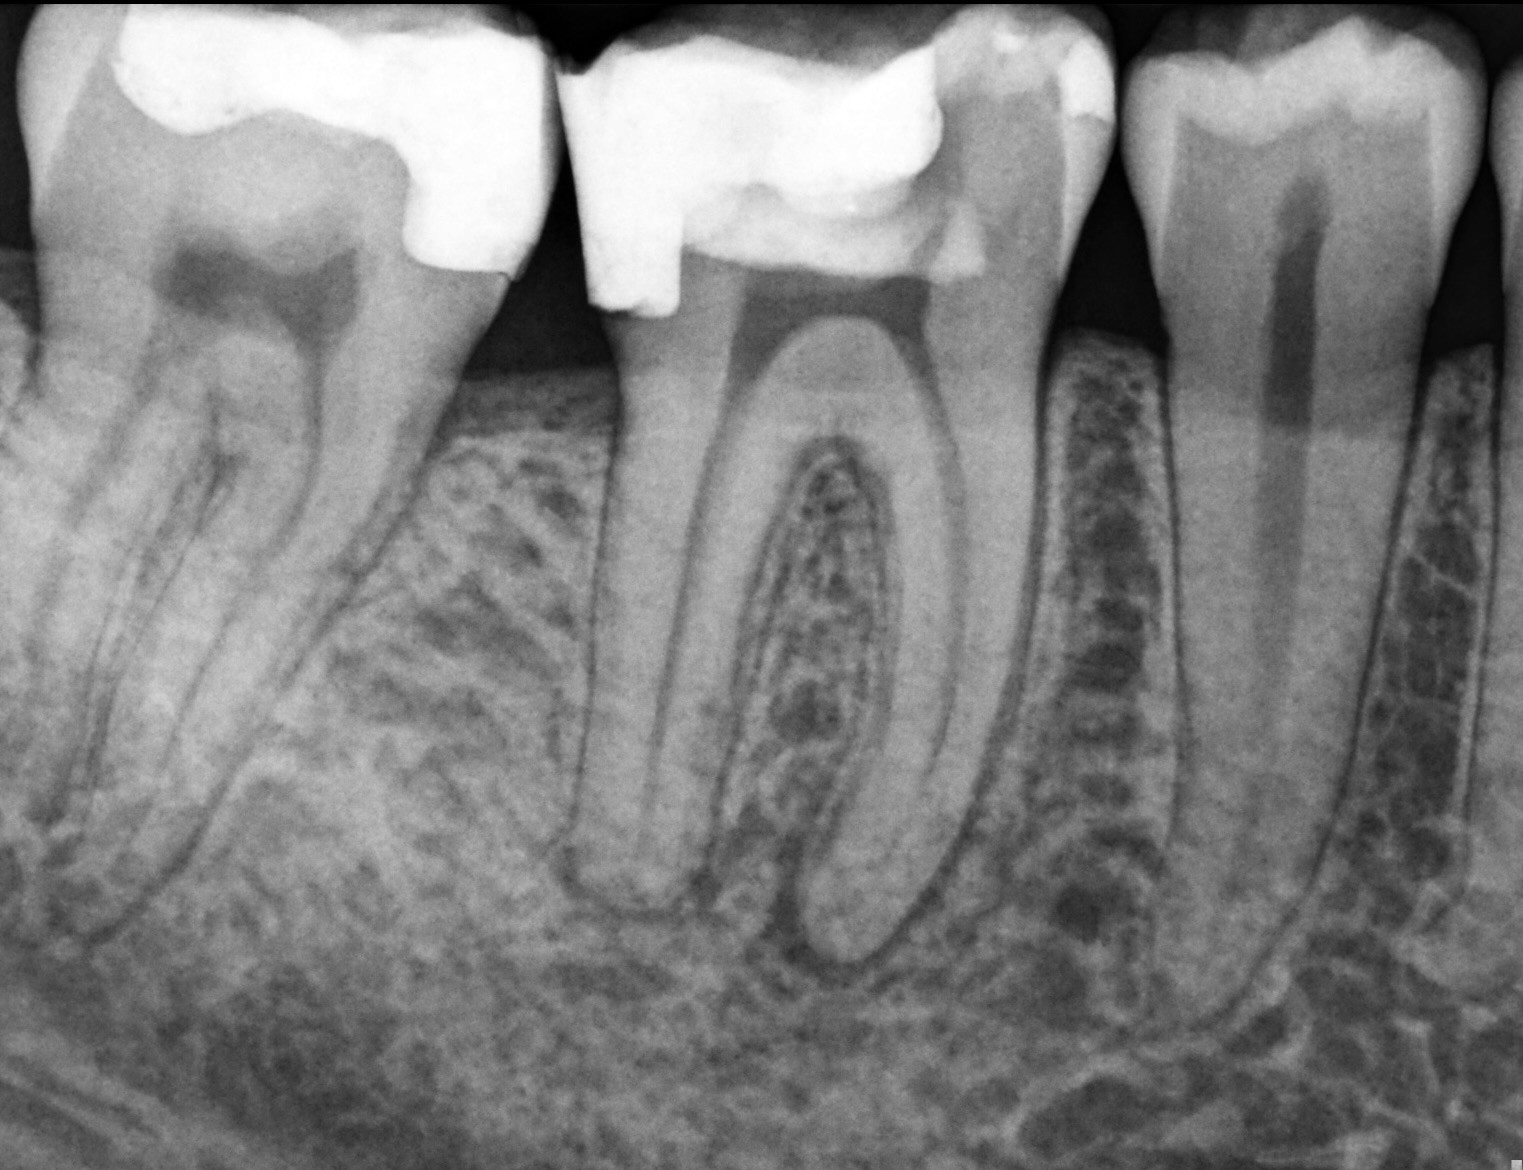

Diagnosis – Digital X-rays and 3D CBCT imaging for accurate assessment.

X-ray Gallery